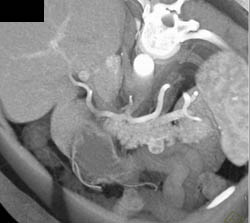

Collaterals Around Stomach Due to Splenic Vessel Occlusion